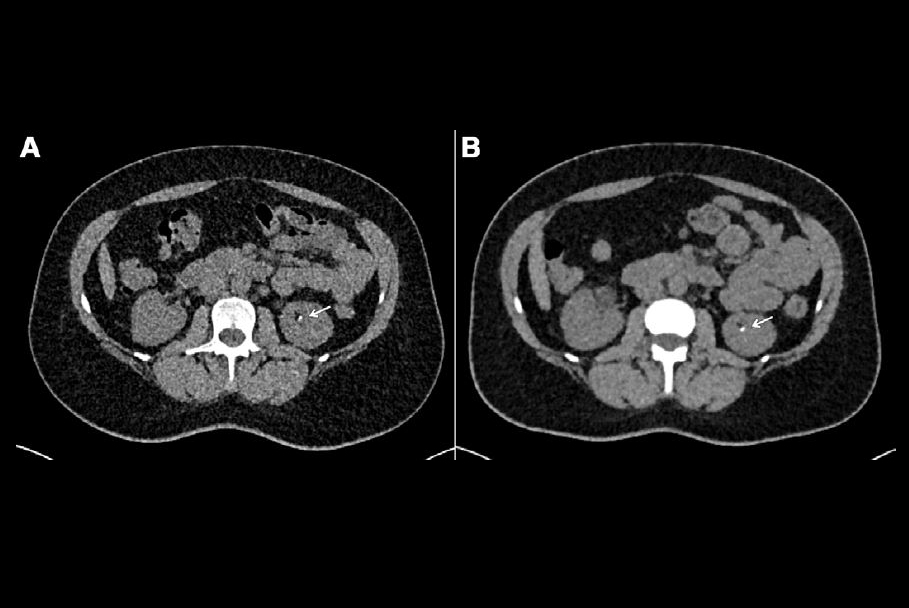

In a third talk, presenter Dr. Jakob Weiss of the University Medical Center Freiburg in Germany shared results from a study that explored the benefits of using artificial intelligence (AI) and PCCT to image the spine post surgery.

Weiss and colleagues conducted a study that included 32 patients referred for PCCT of the spine after surgical placement of metal implants. Four radiologists compared the image quality of the PCCT exams to conventional CT exams, and Weiss's team evaluated radiation dose used for each type of exam.

The group found that the four readers ranked image sharpness on PCCT imaging as significantly higher than on conventional CT (p = 0.009) and noise as significantly lower (p < 0.001). Radiation dose was also significantly lower, at 8.83 mGy compared to 15.7 mGy.

"[PCCT] of the spine with high keV reconstructions provides significantly sharper images and higher diagnostic confidence in patients with metallic implants while radiation dose was significantly reduced," Weiss concluded.